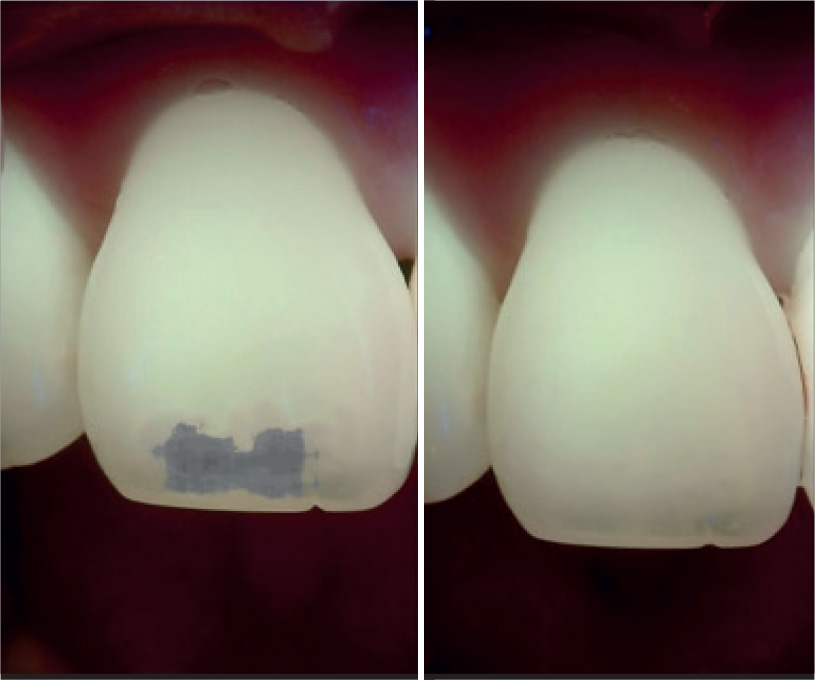

Le lesioni sono state nuovamente mordenzate e asciugate. Questo passaggio è stato ripetuto per tre volte su 21 e quattro volte su 11. Dopo aver valutato la scomparsa della lesione è stata eseguita infiltrazione con Icon-infiltrant per 3 minuti, asciugatura con aria, passaggio di filo interdentale e quindi fotopolimerizzazione per 40 secondi. Viene quindi effettuata una seconda applicazione di infiltrante per 1 minuto e successiva fotopolimerizzazione per 40 secondi. Prima di rimuovere la diga viene fatto vedere al paziente il risultato ottenuto. Viene effettuata valutazione fotografica del risultato finale.

valutazione fotografica del risultato finale